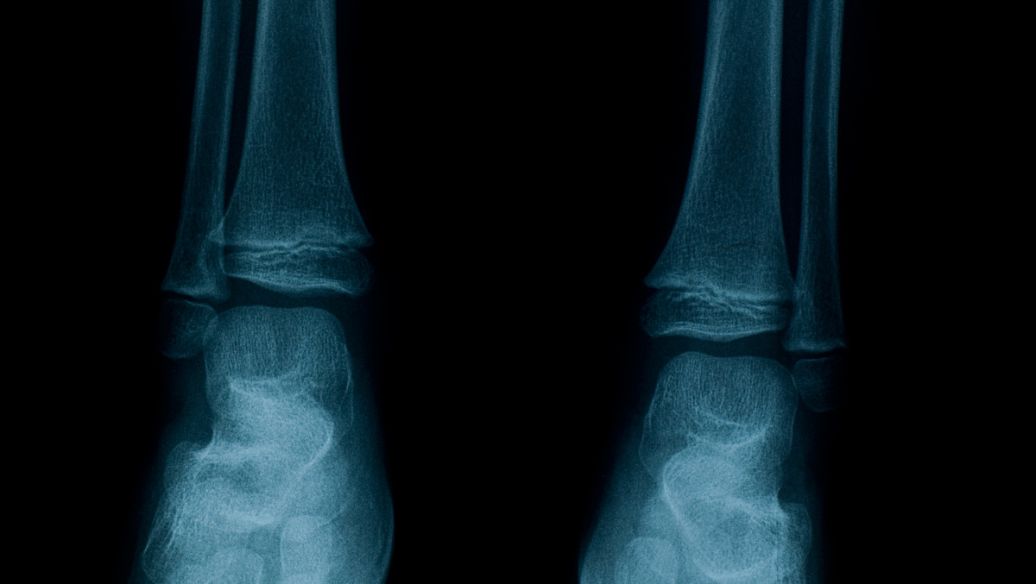

?腫瘤所致骨軟化癥(OOM)初起時(shí)癥狀無特異性,出現(xiàn)骨與肌肉疼痛、疲倦乏力,繼而發(fā)生骨折。兒童少年常有步態(tài)異常、下胺彎形。低腎小管最大磷酸鹽重吸收力/生長激素釋放激素(TmP/GRH),低磷血癥。腸對(duì)磷吸收欠佳。血清1,25一(OH)2一D3較低。影像學(xué)見骨軟化癥。引起疾病的腫瘤多較小,生長緩慢,多數(shù)屬源于中胚層的腫瘤,但亦見于癌癥。腫瘤切除后疾病好轉(zhuǎn)。

初起時(shí)癥狀無特異性,出現(xiàn)骨與肌肉疼痛、疲倦乏力,繼而發(fā)生骨折。兒童少年常有步態(tài)異常、下胺彎形。低腎小管最大磷酸鹽重吸收力/生長激素釋放激素(TmP/GRH),低磷血癥。腸對(duì)磷吸收欠佳。血清1,25-(OH)2-D3較低。

證實(shí)診斷的依據(jù)是檢出并定位基礎(chǔ)腫瘤。必須考慮到其他腎臟磷酸鹽流失病?;颊?尤其是成人)既往血清磷酸鹽水平正常一般支持診斷為TIO。由于腫瘤體積較小且位于隱蔽部位,常規(guī)成像技術(shù)很難對(duì)其定位。間葉腫瘤通常表達(dá)生長抑素受體,因此通過111銦噴曲肽閃爍成像(放射性標(biāo)記的生長抑素類似物奧曲肽的掃描技術(shù))可以定位部分患者的腫瘤。全身MRI、(18F)FDG-PET/CT等其他影像學(xué)檢查也可用于定位腫瘤。體靜脈采樣檢測FGF23也已用于定位致病腫瘤,但該技術(shù)更適合確定所識(shí)別的腫塊是否產(chǎn)生FGF23。腫瘤體積較小且位于骨骼這些特點(diǎn)限制了識(shí)別和定位腫瘤的能力,推定診斷為TIO患者的腫瘤檢出率為65%-80%。